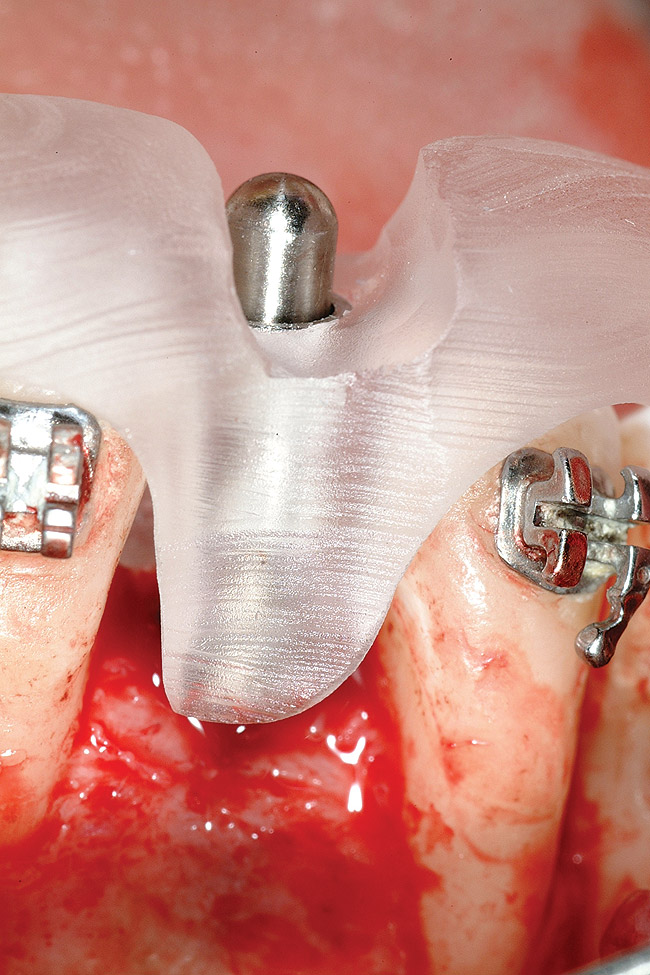

Figure 18   Implant placement with resulting facial dehiscence. Cortical perforations placed to promote angiogenesis.

Figure 18

Figure 19  Mineralized freeze-dried bone allograft hydrated with platelet-derived growth factor covering root dehiscences and implant dehiscence.

Figure 19

Following the first goal of orthodontia—moving tooth No. 22 to a proper functional and anatomical position—a periodontal reevaluation was performed, demonstrating an improvement in short- and long-term tooth prognosis. At this time, the decision was made to abort continual extrusion of teeth Nos. 21 and 22, although some attachment level discrepancy remained between Nos. 21 and 22 (Figure 14). Implant diagnostics ensued and included mounted study models and a diagnostic wax-up. A scanning appliance was created to demonstrate the desired prosthetic outcome requirements, and the patient was referred for computed tomography (CT) scans. CT scan assessment demonstrated successful orthodontically directed GBR to allow implant placement (Figure 15 through Figure 16). Only minor GBR therapy would be needed and could be accomplished simultaneously with implant installation. Guided implant placement occurred, using an open flap approach (Figure 17). During surgery, root dehiscences were noted on teeth Nos. 21, 22, 24, and 25, as well as the anticipated dehiscence following implant placement at No. 23 (Figure 18). A positioning reference (index) was secured after implant placement to facilitate a provisional prosthesis at stage II surgery. Cortical perforations then were placed adjacent to the implant to encourage angiogenesis (Figure 18), and mineralized freeze-dried bone allograft enhanced with platelet-derived growth factor was placed over the dehiscences for purposes of guided tissue regeneration and GPR (Figure 19). A highly resorbable collagen membrane was placed to stabilize the allograft. The flap was coronally repositioned, and primary-intention wound healing was achieved (Figure 20 and Figure 21). Following 4 months of stage I surgery, implant uncovery and immediate provisionalization was performed in conjunction with connective tissue grafting. Final orthodontic tooth movement then ensued, using the implant as anchorage to optimize end-tooth movements, interroot separation, and the cuspid-protected occlusal scheme. A final impression then was secured, and a zirconia abutment (Figure 22) with an all-ceramic restoration was fabricated for the prosthetic phase completion of No. 23 (Figure 23] through Figure 25).